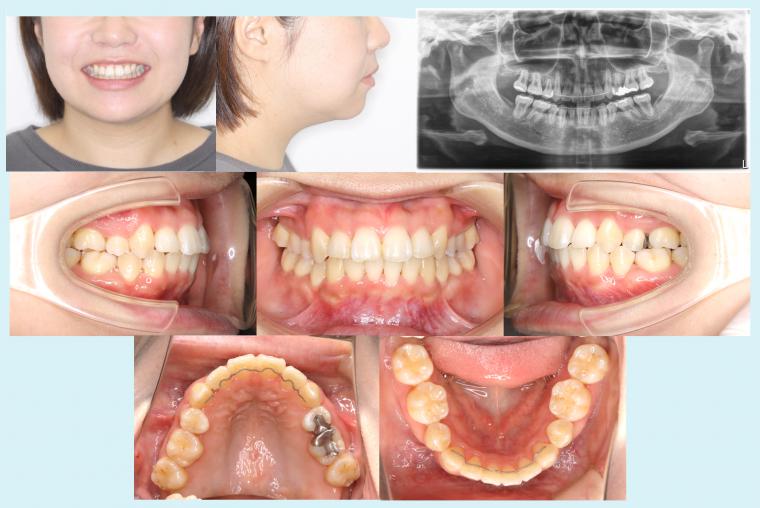

#49 重度叢生症例